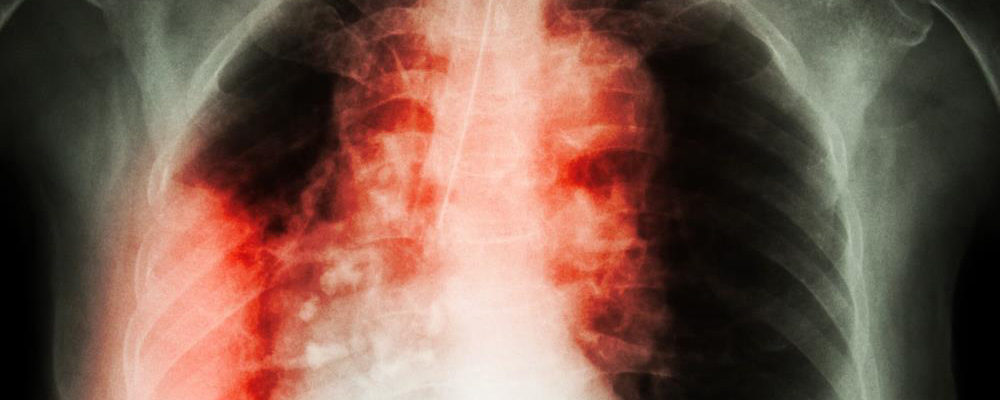

(Natural News) A Canadian research team announced that it has found the reason for the appearance of pulmonary fibrosis in a number of lung cancer patients who underwent thoracic radiotherapy. They found a connection between genes on a certain chromosome and the development of lung injuries triggered by radiation. The researchers were investigating chromosome 6, one of the 23 pairs… |